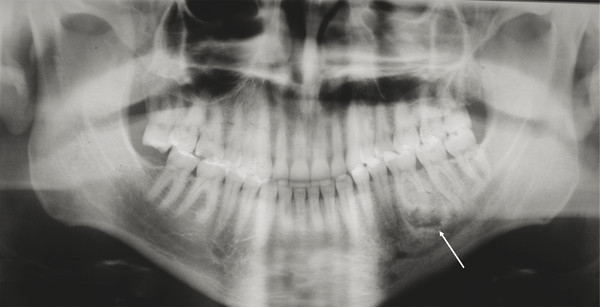

The most common nonodontogenic cyst in childhood is the traumatic or simple bone cyst (SBC). Typically, the patient has an asymptomatic radiolucent lesion of the mandible, with no clinical swelling or any other abnormalities on examination (Fig. 9‑3). The lesion favors the male population and presents in the first two decades of life. The radiographic imaging warrants surgical exploration and curettage in order to rule out an epithelial lined cyst or tumor. The clinical finding is an empty bony cavity with very little tissue, if any, to submit to pathology. If the lesion is large enough or near the condylar head, a bone graft may be warranted, but typically, after curettage of the bony wall, the lesion will fill in with normal bone over time.